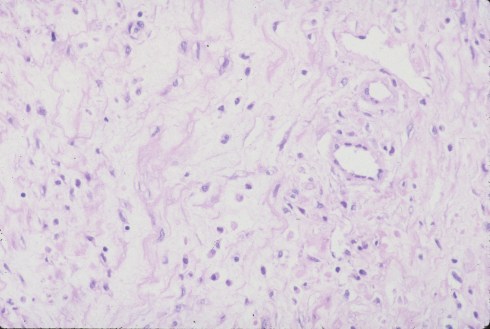

Fig 2: At higher magnification the inflammatory cells appear to be predominantly mononuclear. (H&E 25x)

Fig 3: In another area a more edematous, less cellular matrix is evident. (H&E, 25x)